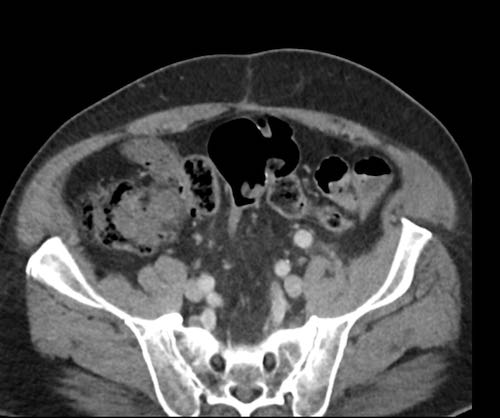

Ca lâm sàng 2

Cuộn qua các lát cắt.

Bạn có thể phát hiện tất cả các tổn thương cấy ghép phúc mạc không?

.jpeg)